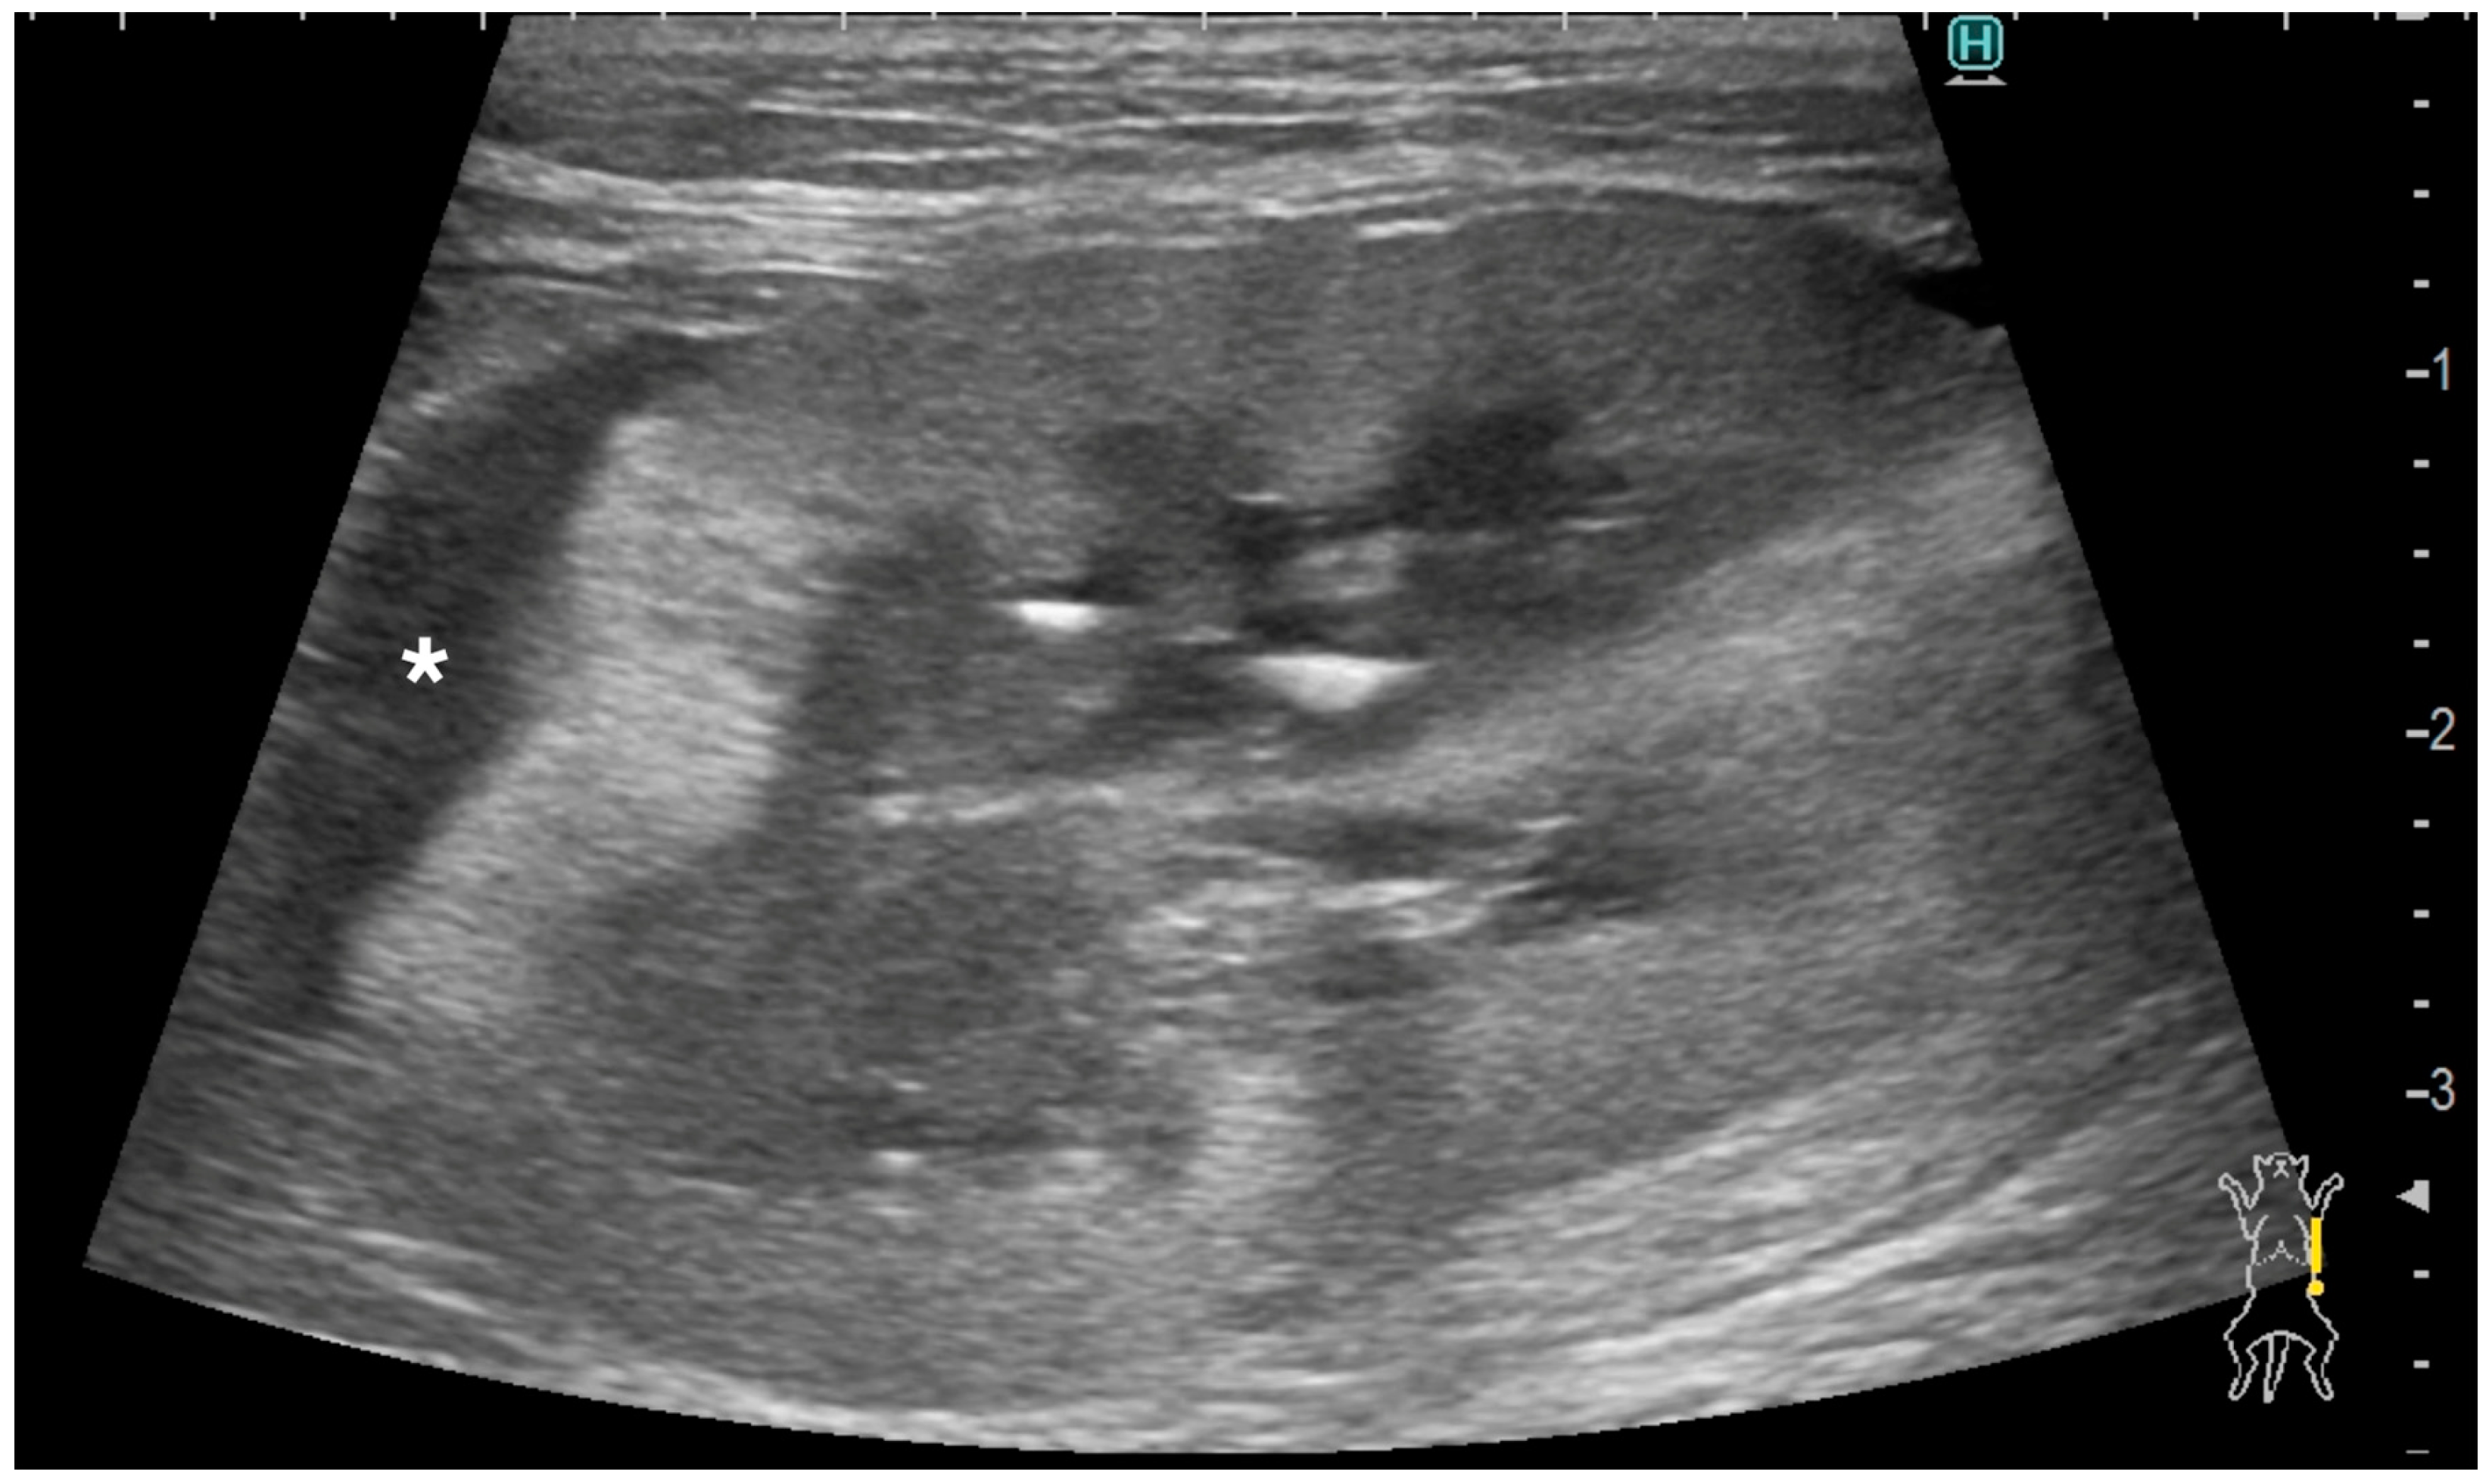

3.4. Ultrasonographic Findings of the Rest of the Kidney

Ultrasonographic findings of renal parenchyma are listed below. The renal cortex was evaluated as normal in two kidneys (2/9) and abnormal in seven kidneys (7/9). In those 7 kidneys with abnormal renal cortices, the renal cortices were diffusely hyperechoic in three kidneys (heterogeneous in two and homogenous in one, Figure 2), and focally hyperechoic in four (single in two and multifocal in two, Figure 4).

A distinctive pattern was observed in three out of seven abnormal renal cortices, which showed hypoechoic striations within the hyperechoic areas (Figure 4). These hypoechoic striations of the renal cortices appeared to be associated with subcapsular thickening, as most of them were located just underneath the subcapsular thickening areas. Corticomedullary distinction was evaluated as well-defined in one kidney (1/9), ill-defined in seven kidneys (7/9), and completely effaced in one kidney (1/9). The renal pelvis was very mildly dilated in two kidneys, of which the diameter was 1.3 and 1.9 mm, and the others showed no dilation. Small multifocal mineralization was observed in the renal cortices and along the renal diverticula in two kidneys, both of which belonged to the same cat. A renal cortical cyst was present in one kidney. Two kidneys from two cats, both of which were diagnosed as pulmonary carcinoma with renal metastasis, exhibited a renal nodule. These nodules were hyperechoic to the adjacent renal cortex, and their sizes were 5.6 mm and 9.3 mm.

Figure 4. Ultrasonographic image of a kidney with metastatic pulmonary carcinoma (case 4, left kidney). A homogeneously hypoechoic subcapsular thickening (*) was present. The renal cortical and renal capsular margins were irregular. Hypoechoic striations were observed within the hyperechoic areas in the renal cortex.